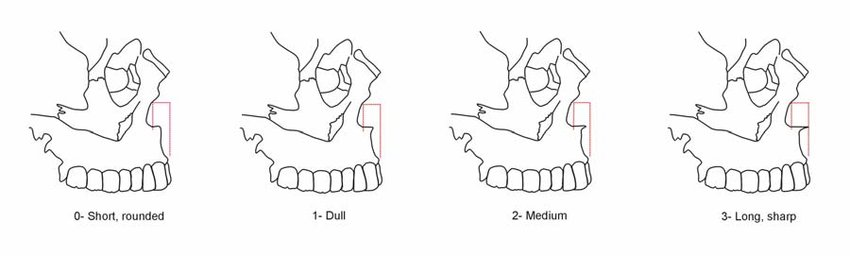

3. USO (U shaped Osteotomy)

- Bone cut shaped like a "U" around the piriform rim that mobilizes the anterior maxillary wall and ANS as one segment. The segment is advanced, rotated, and fixed with small screws.

- Projects the ANS and paranasal rims forward.

- Why vs graft/implant: Uses actual bone for a cleaner contour. Likely superior to both implants and especially grafts if done right.

- USO is a "rare" osteotomy. There are few confirmed cases online, and fewer doctors who publicly say they perform it.